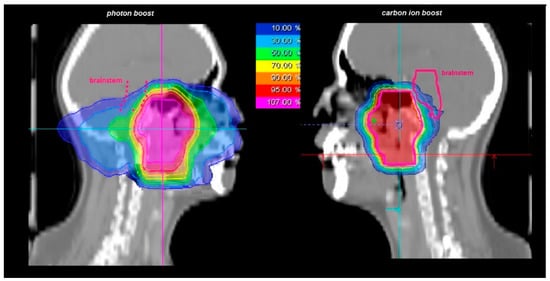

| 50 Gy/2 Gy IMRT + 24 Gy/3 Gy (RBE) C12 | 5 (19) |

| 56 Gy/2 Gy IMRT + 18 Gy/3 Gy (RBE) C12 | 21 (81) |

| median total dose | 74 Gy (RBE) (72–74 Gy (RBE)) |